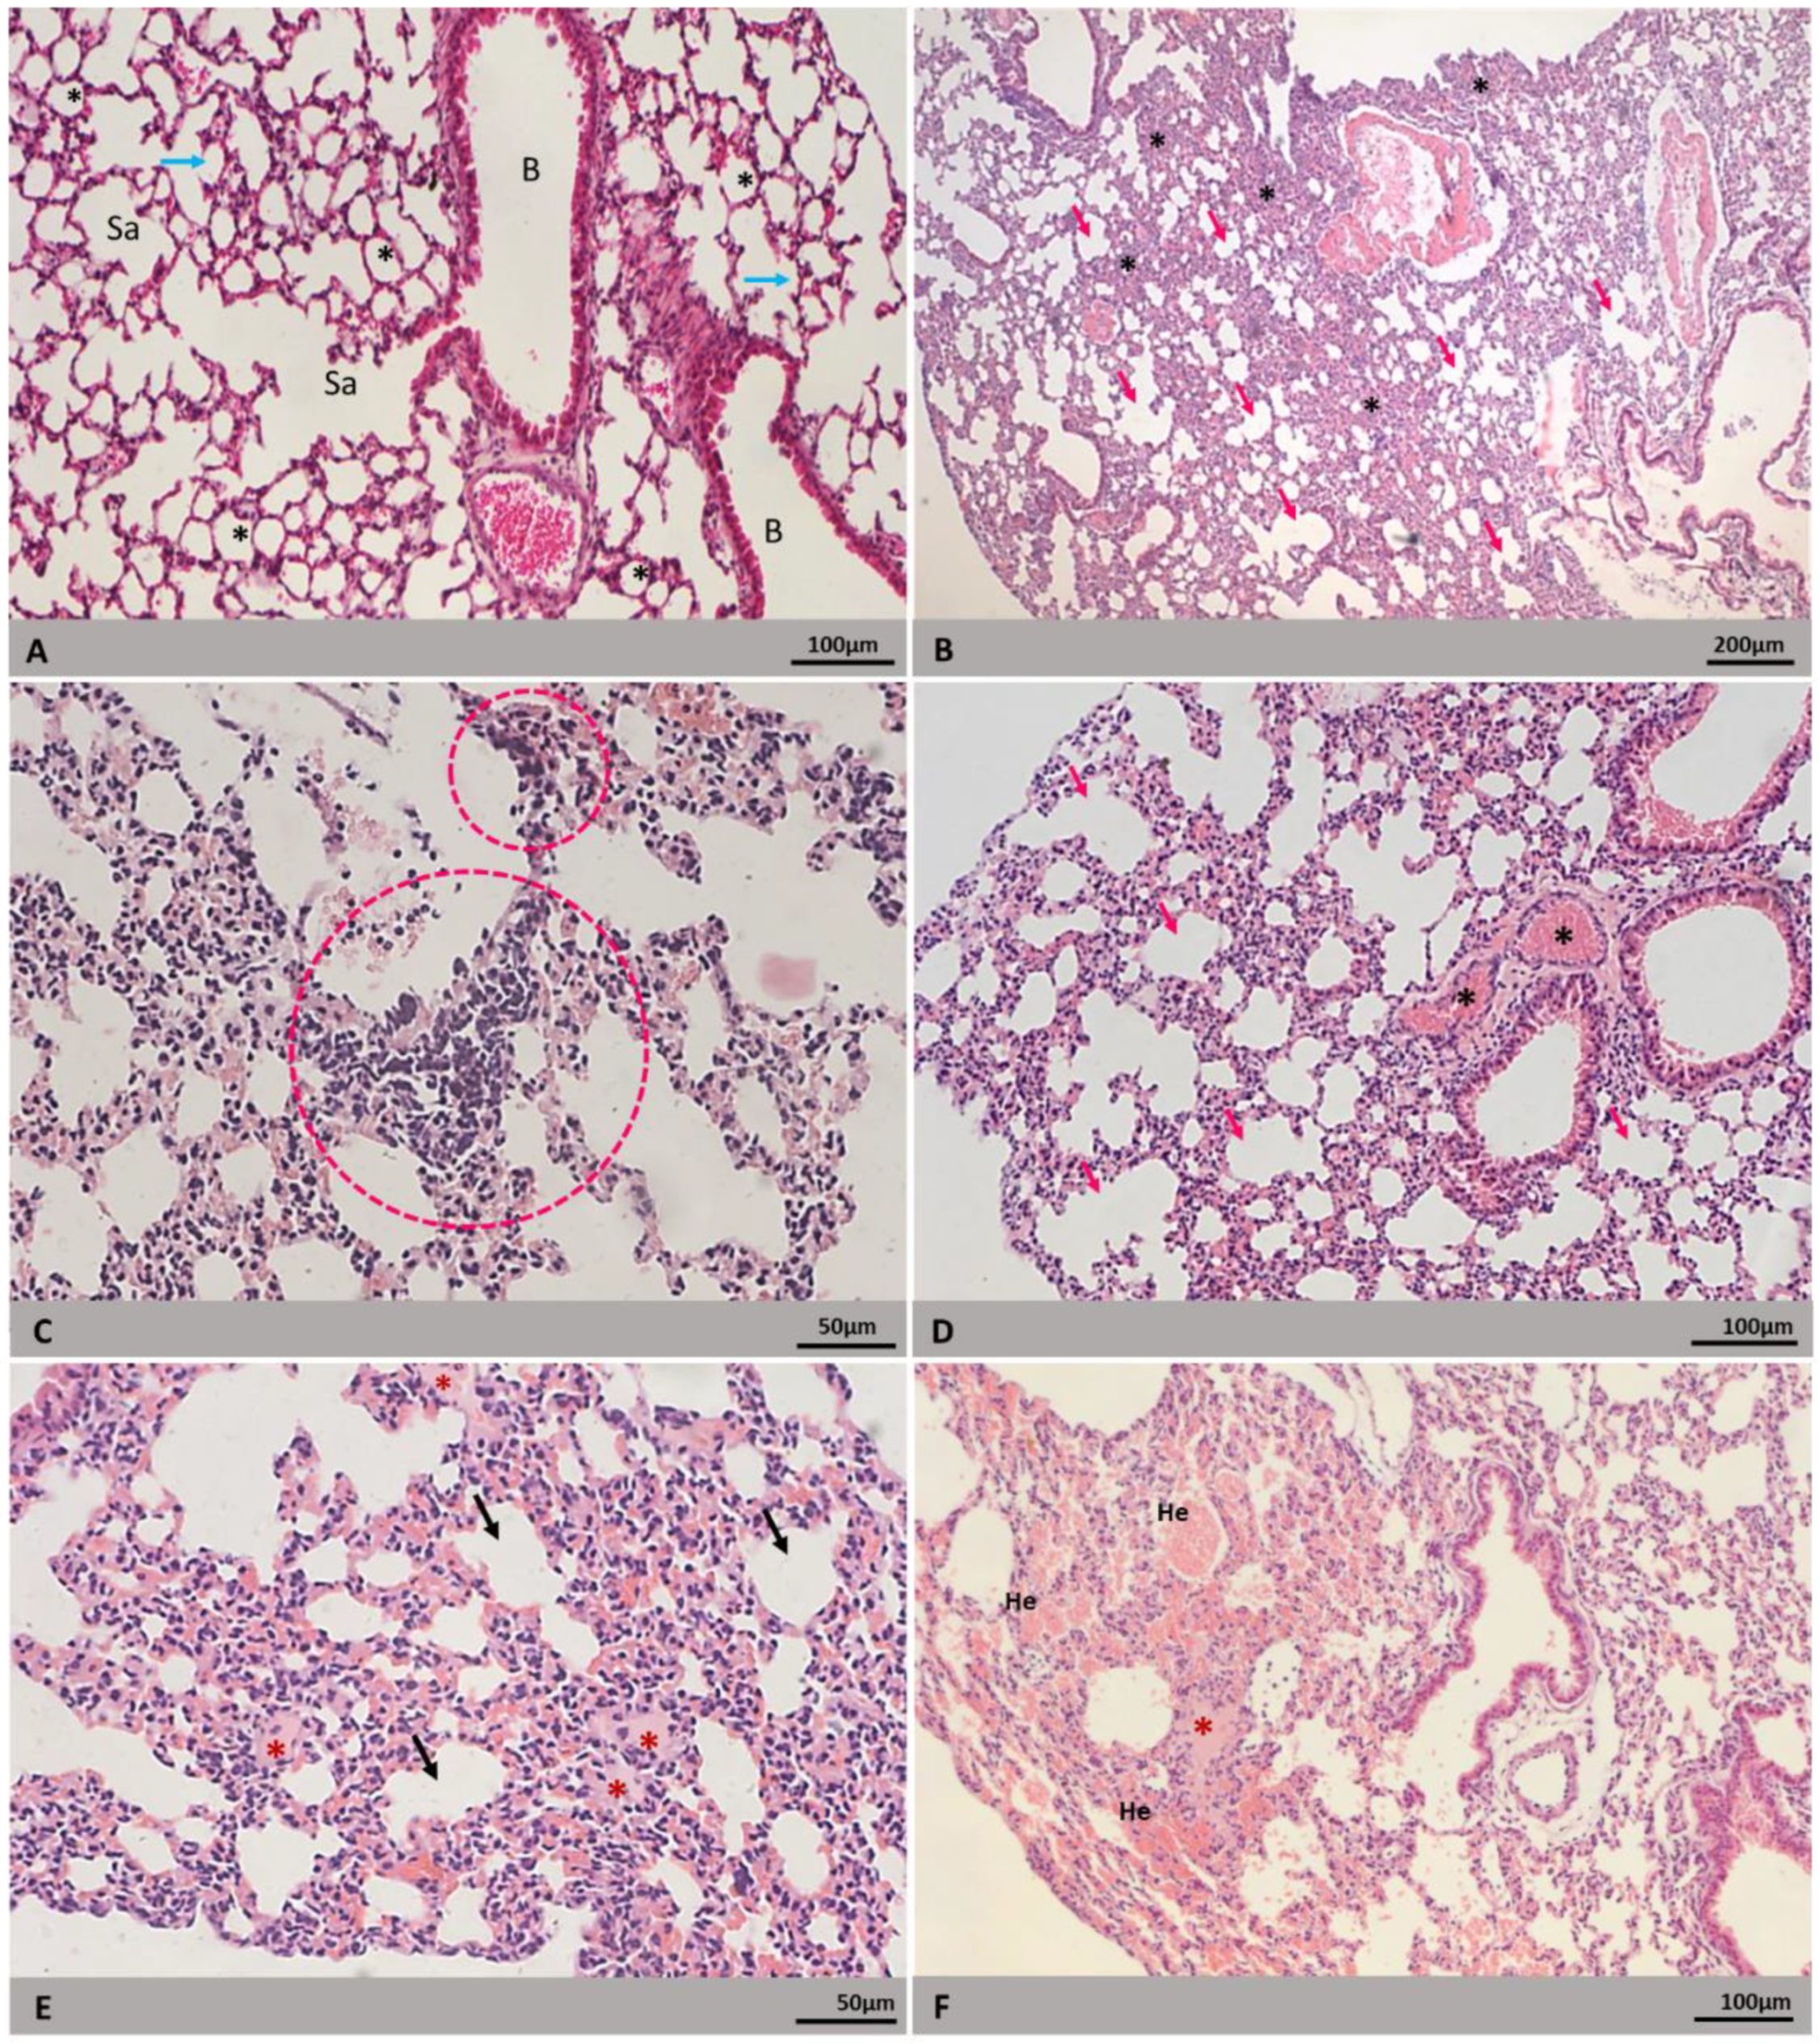

| Heart | Inflammatory infiltrate | 7/10 (70) | 9/10 (90) | 17/20 (85) |

| Cytoplasmic rarefaction | 7/10 (70) | 4/10 (40) | 11/20 (55) | |

| Increased cellularity | 2/10 (20) | 4/10 (40) | 6/20 (30) | |